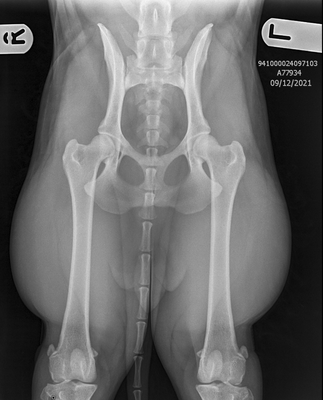

Hip & Elbow x-rays

Perhaps one of the most well known health testing in dogs, hip and elbow x-rays taken to check for signs of dysplasia. Once taken by a qualified vet the x-rays are then sent to a scoring board dependent on country of residence or personal choice of the breeder. To the right, is a comparison of the results across the most common available testing organisations.

The organisation which we primarily use for our program is BVA.

Hips: Under the BVA scheme, the marking of hips is broken down into 9 sections, the maximum marks in any one section is 6, and the maximum overall is 106. The aim is to obtain the combined lowest number possible, the best result possible being a 0. Please view the example images of our dogs results attached above to see the 9 possible sections.